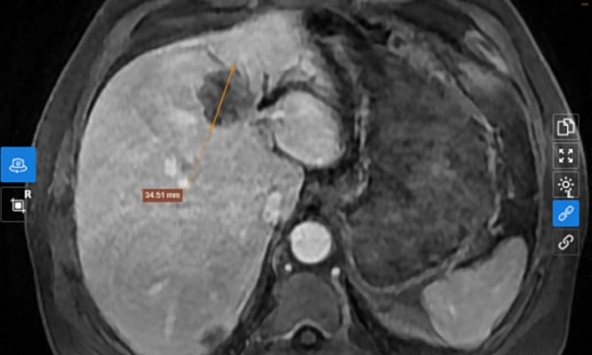

Tuy nhiên, sau khi siêu âm và chụp cắt lớp vi tính, bác sĩ phát hiện dị vật hình xương cá dài 14x2mm đã xuyên qua thành thực quản cổ, nằm sát động mạch cảnh chung - một vị trí cực kỳ nguy hiểm.

| Hình ảnh chiếc xương cá xuyên qua thành thực quản cổ |